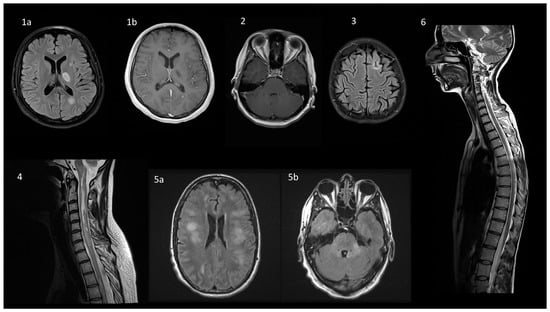

6. Neuroimaging

| MRI image |